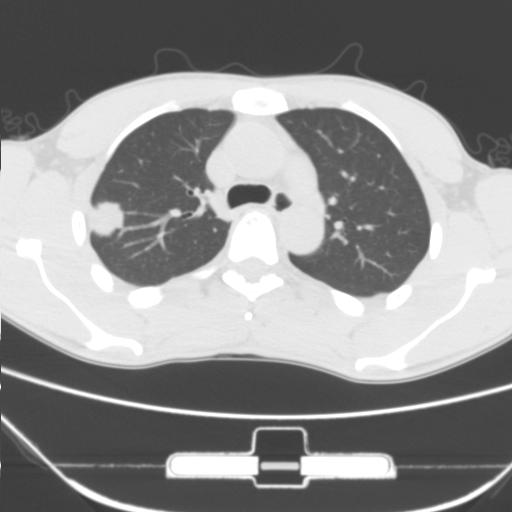

右肺上叶后段近胸膜下结节样异常密度灶,似见分页及毛刺,考虑右肺上叶周围型肺ca,建议穿刺病理检查

缺乏病史,症状体征,但这个孤立结节具备了几乎所有的恶性征象:分叶,毛刺,空泡征,胸膜凹陷征,血管集束。

考虑右肺上叶后段周围型肺癌。